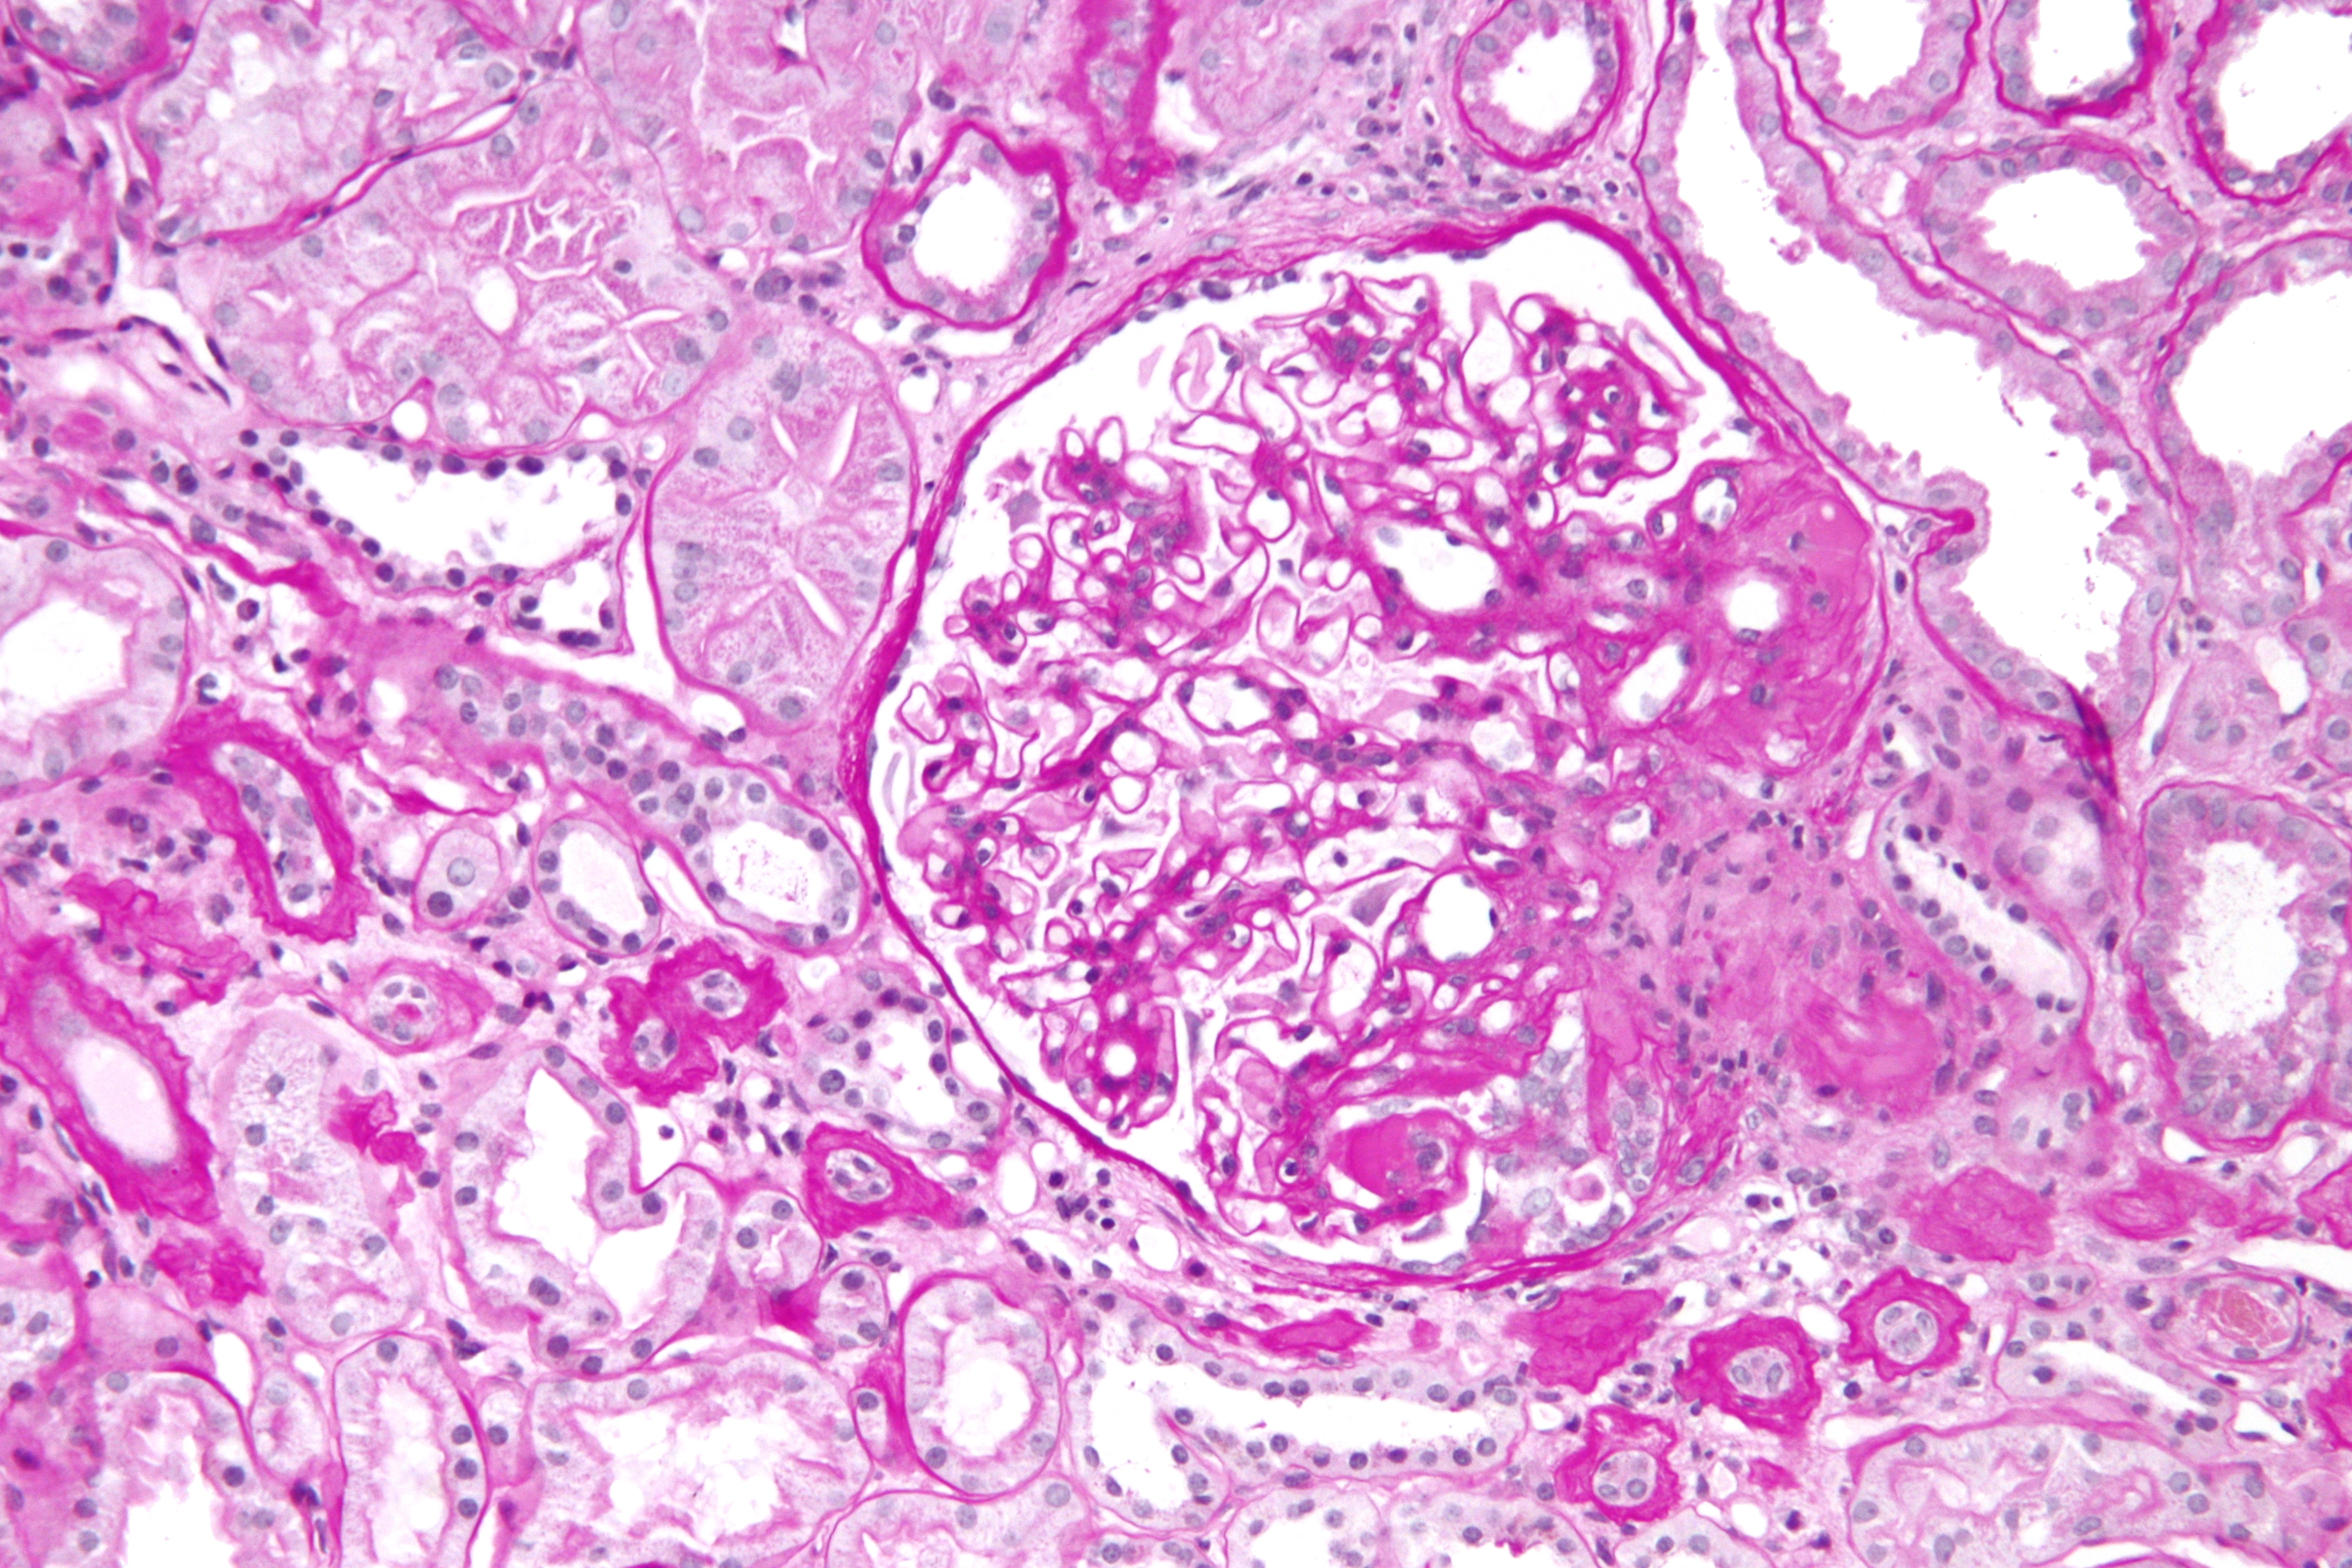

Sparsentán o irbesartán para retrasar el descenso de la función renal en la glomeruloesclerosis focal y segmentaria

28 diciembre 2023

Este ensayo clínico doble ciego se comparó sparsentán, un antagonista dual de receptores de endotelina y angiotensina II, con el tratamiento estándar con irbesartán. Aunque el antagonista dual logró un mayor descenso de la proteinuria, no modificó la pendiente de descenso de la función renal al cabo de dos años de seguimiento. New England Journal of Medicine, 28 de diciembre de 2023.